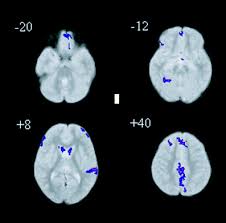

Hypometabolism In Asperger S Syndrome Stock Image C026 1133 Science Photo Library

Hypometabolism In Asperger S Syndrome Stock Image C026 1133 Science Photo Library from media.sciencephoto.com